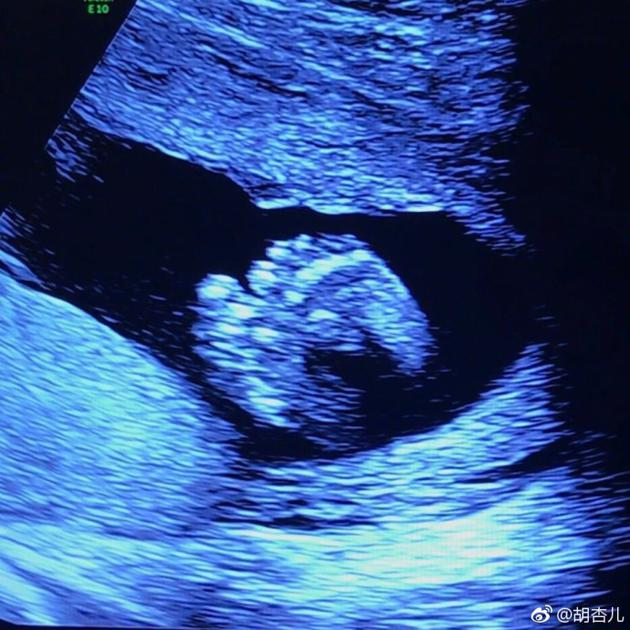

1怀孕一个月胎儿图第一个月的胎儿还是受精卵,被称为胚芽胚胎,长度为02毫米,体重约为1505μg微克,通过B超看宝宝如同一颗很小的松子一直到本月月末,各个器官的原型都会逐渐出现,胎盘脐带都开始发育,胎宝宝的心脏没有一颗罂粟种子大,不过已经开始由跳动了2怀孕一个月胎儿B超图;怀孕初期通过B超检查确实可以观察到一些迹象,但需要注意的是,这个阶段胎儿的器官和结构尚未完全形成,B超图可能显示的信息有限通常情况下,怀孕大约45周时,胚胎在子宫内的影像可能还不明显,而到了6周左右,胚胎的心跳和基本轮廓可能开始显现不过,在怀孕初期,尤其是在前三个月,医生通常建议避免。

第4周,心脏还只是一条管子,但是已经开始跳动了,开始为小人儿输送血液大脑也还是一根小小的神经管,正以惊人的速度生长着,每小时能产生个新的神经细胞第4周末,在B超检查下,已经可以见到7毫米大小的孕囊了,并且每天以1毫米的速度生长 不过每个小人儿发育情况不同,有些人可能要到怀孕第;1怀孕一个月胎儿多大第一个月的胎儿还是受精卵,被称为胚芽胚胎,长度为1厘米左右,体重约为1克,通过B超看宝宝如同一颗很小的松子这里有一些一个月胎宝宝的指标,准妈妈们可以参照一下1胎重约1克2胎长051厘米3五官眼睛鼻子耳朵尚未形成,但嘴和下巴的雏形已经。